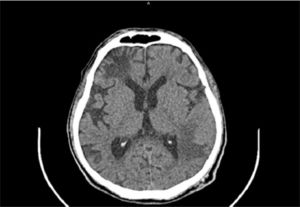

At the time the patient attended the emergency unit he was oriented but presented a compromise of executive functions like calculation and planning, also showing right patellar hyperreflexia. Computed Tomography (CT) of the central nervous system with contrast medium demonstrated left frontal subcortical hypodensity and left temporo-parietal hypodense lesion (Fig. 1); both lesions did not capture contrast medium. CT also showed extensive subcortical atrophy, without displacement of lesions in the midline. No other lesions were identified.

A cerebrospinal fluid sample (CSF) of the patient was collected and sent to the clinical laboratory of the hospital for biochemical, bacteriological and parasitological analyses, revealing a decreased concentration of glucose and an increased concentration of microproteins (Table 1). The sample was centrifuged at 2500 rpm for 5 min and the sediment was placed into a Neubauer chamber for leucocyte and erythrocyte count. During the visualization under the microscope, the presence of high-motile trypomastigotes was observed (Fig. 2). This sediment was fixed using methanol and Giemsa stains were performed.

Diagnosis of Trypanosoma cruzi: (a) Giemsa stain of the CSF sample that revealed the presence of trypomastigotes; (b) Giemsa stain of epimastigotes after the culture procedures applied; (c) PCR that confirms the diagnosis of T. cruzi. M, Gene ruler 100 bp DNA ladder (Thermo Fisher, USA); S, sample; PC, positive control (DNA from T. cruzi TCR4); NC, negative control.

An aliquot of the CSF sample was transported to the Faculty of Microbiology of the University of Costa Rica for culture in Vero cells and then, in LIT culture medium for epimastigote growth and parasite´s isolation. DNA extractions and PCR analyses using the pair of primers 121 and 122, which target to the 330-bp variable regions of the T. cruzi Kinetoplastid Minicircle genome (kDNA)15 were also performed (Fig. 1). Another aliquot was sent to a reference center (INCIENSA), which also confirmed the presence of T. cruzi using molecular and serological techniques.